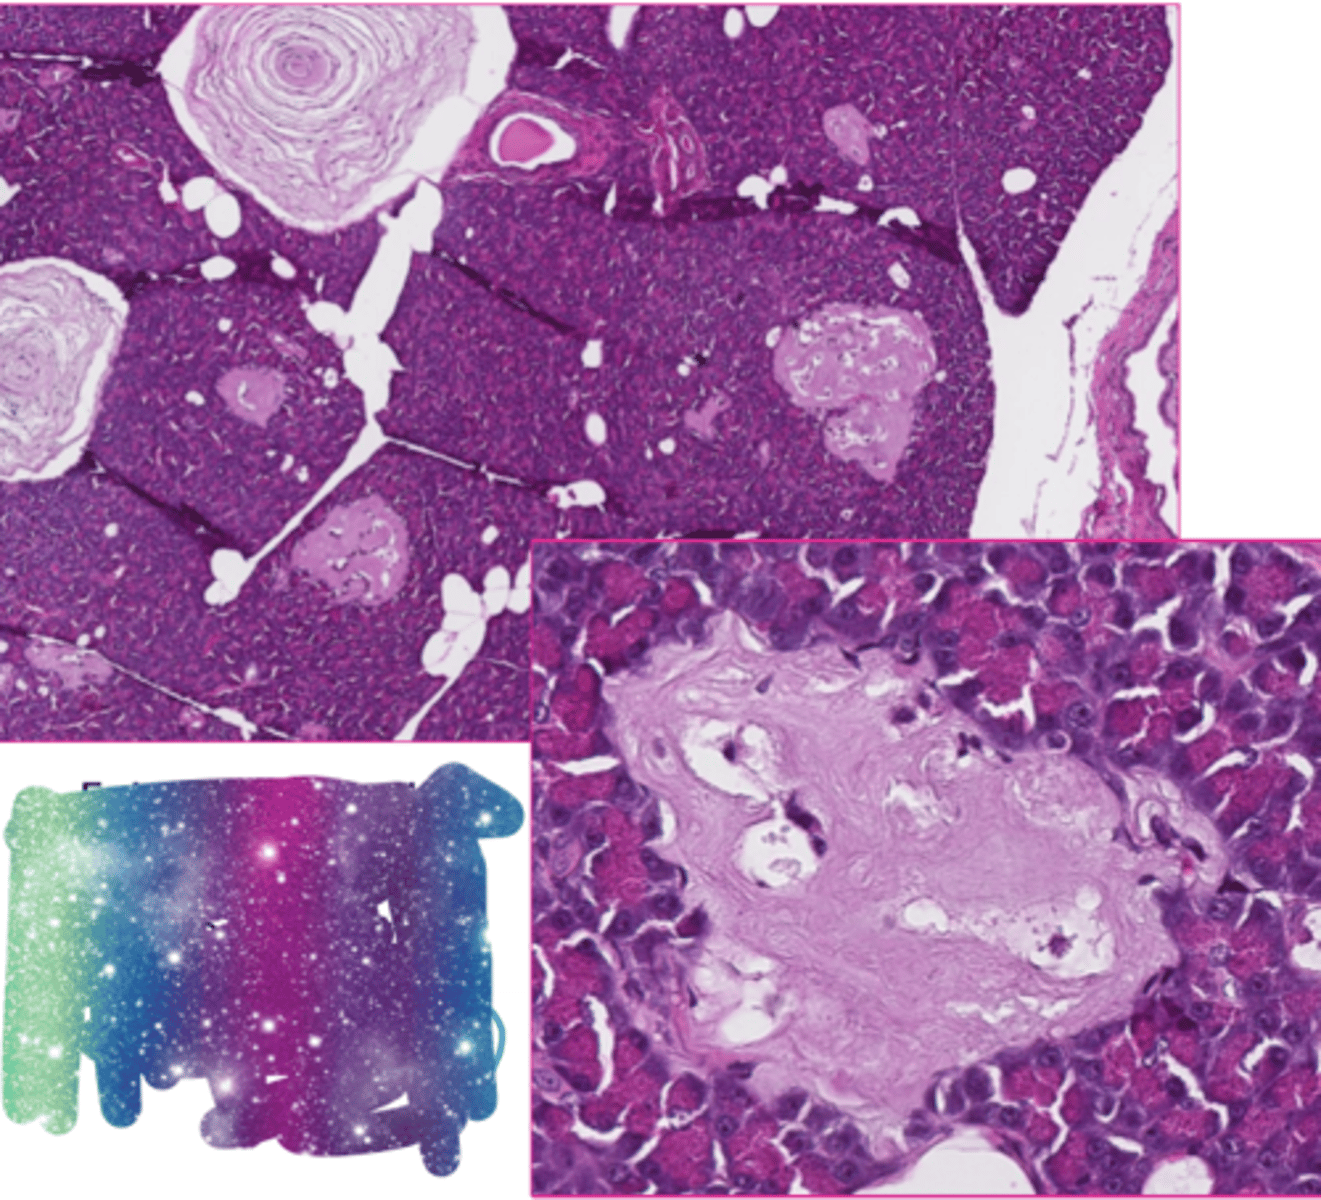

corpora amylacea

What extracellular accumulation?

These are both examples of what type of amyloid?

Islet amyloid peptide secreted by beta cells in pancreatic islets in cats

Beta-amyloid in cerebral cortex of aged dog with canine cognitive dysfunction